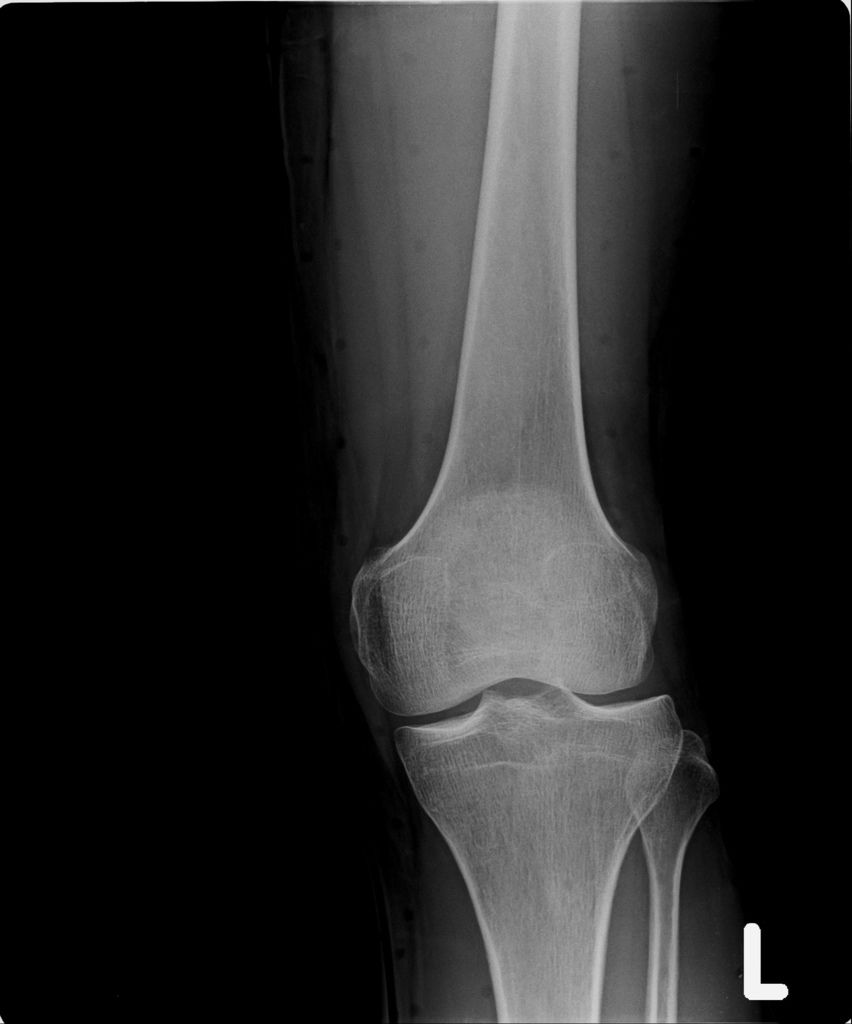

左腳X光↓

左腳X光照↓

進入門診前,我自認為手比腳恢復還快,因為比起一開始,手指比較能出力了,手腕可轉動的範圍也變大了。腳因一直用副木石膏固定住,不能動,所以也不知恢復多少。進入門診後,黃醫師說斷裂的骨頭都沒移位。手沒什麼進展(骨頭不會長那麼快),腳的部份下回再來復診時,可能會恢復的較快了。